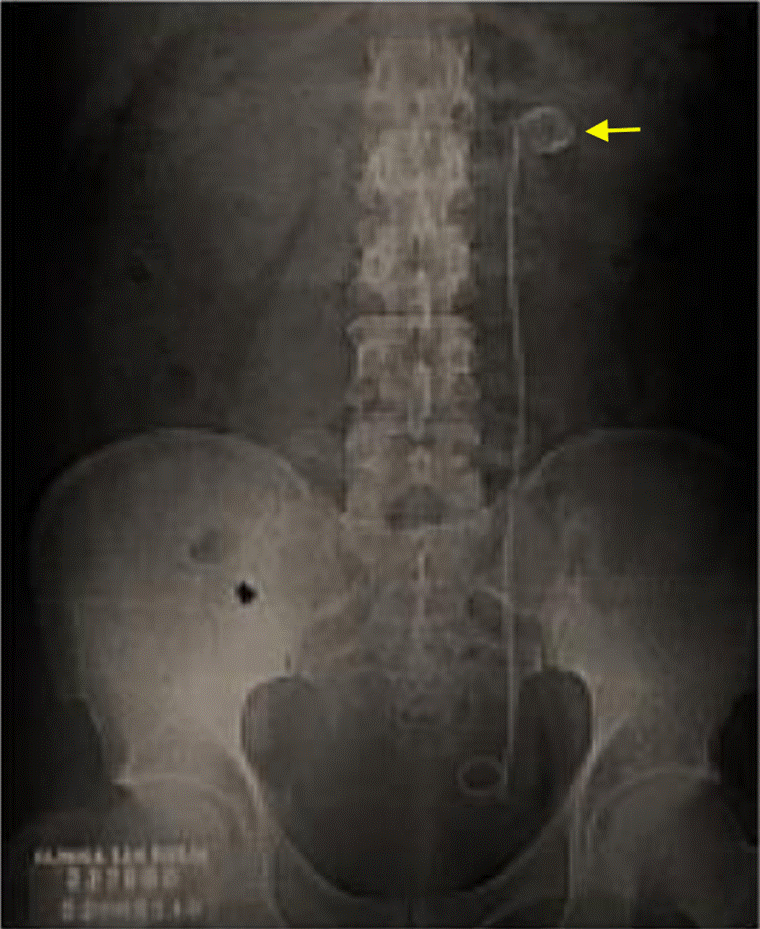

Durante su estancia hospitalaria, el paciente presentó expulsión espontánea de lito, con posterior descenso de azoados desde 2,48 mg/dL de creatinina al ingreso, hasta 1,5 mg/dL, por lo que fue llevado a implante de catéter doble J sin complicaciones. Luego de 21 días de antibiótico, los hallazgos radiológicos (Figura 4) mostraron una disminución de gas en el parénquima renal, por lo cual se le dio el alta hospitalaria y se definió el control para retiro de catéter doble J ambulatoriamente.

En el primer caso aquí reportado el paciente cursaba con obstrucción secundaria a cálculos ureterales, por lo que la derivación de la vía urinaria y el drenaje del gas se logró mediante la colocación de un catéter doble J. Es de mencionar que una persistencia de gas en la imagen radiológica no implica infección activa y que el tratamiento conservador basado en antibióticos y fluidoterapia puede llevar a la resolución del cuadro con expulsión espontanea de cálculos y mejoría de la función renal12.

A partir de los hallazgos se confirma lo encontrado en otros estudios con respecto al logro de resultados exitosos a partir de un diagnóstico temprano y una combinación de intervenciones médicas y quirúrgicas oportunas, cuando sean necesarias, junto con un monitoreo meticuloso del progreso mediante evaluación radiológica secuencial, bien sea con radiografía como en el caso 1, o con tomografía como en el caso 2.